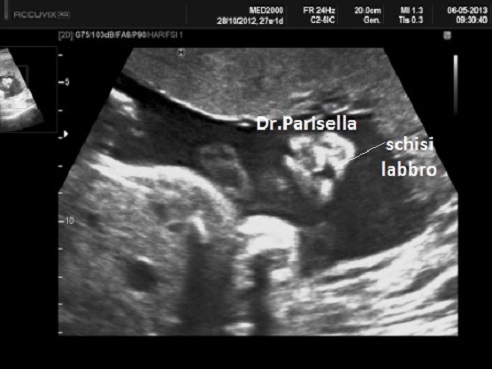

• Anomalie cranio-facciali: ipertelorismo,labiopalatoschisi, micrognazia;